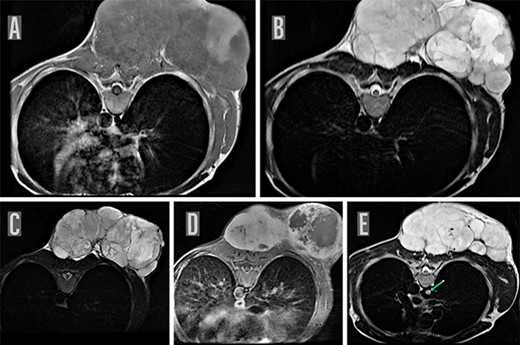

On local examination, he had a 20 × 20 cm2 tender hard mass at left upper back with overlying ulceration and discharge (Fig. 1). Magnetic resonance imaging (MRI) of the chest with contrast revealed a large lobulated heterogeneously enhancing soft-tissue mass in the subcutaneous plane of the posterior aspect of the chest wall along with a suspicious nodule in the azygous lobe of the right lung, which warranted further investigation (Fig. 2). Biopsy of the mass reported spindle cell sarcoma with possibility of neuronal cell origin. Immunophenotyping was advised for further confirmation but could not be done due to lack of resources.

MRI chest. MRI of the chest on axial sections reveal a large well defined lobulated soft-tissue mass in the subcutaneous plane of the posterior chest wall, predominantly iso-hypointense on T1WI (A) with few areas of T1 hyperintensity and hyperintense on T2W image (B) and STIR images (C) and showing heterogenous enhancement with few central non-enhancing areas of necrosis on post contrast T1W images (D). Multiple internal septations were noted within the lesion with significant external contour bulge abutting the posterior chest wall muscles as well as bilateral posterior paraspinal muscles suggestive of a neoplastic process, possibly a mesenchymal tumor. MRI chest also shows a suspicious nodule (8 mm maximum diameter) appearing hyperintense on T2W image in the azygous lobe of right lung (indicated by green arrow) (E).